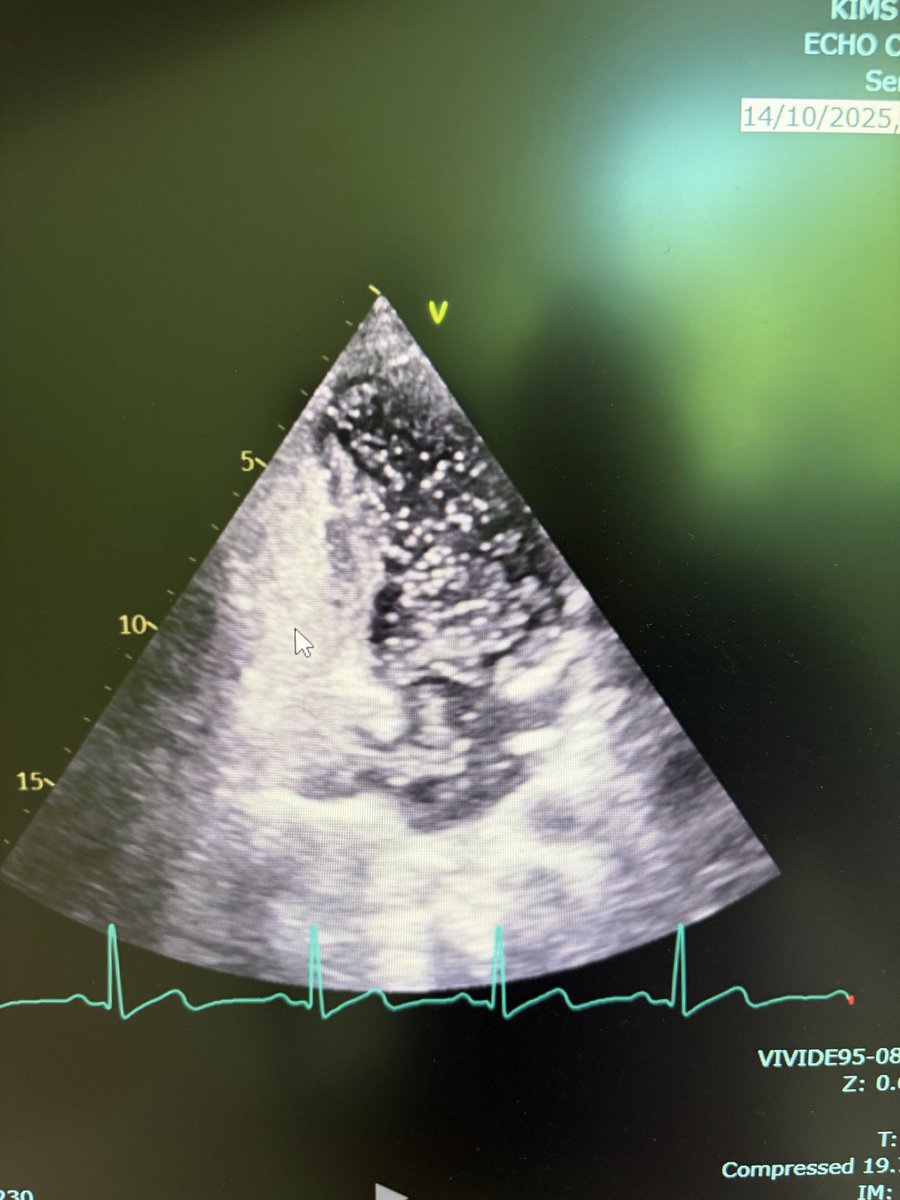

Two weeks ago, a 54-year-old patient recovering from open-heart surgery (CABG) suffered a major stroke. • Symptoms: Sudden inability to speak + right-side paralysis. • Action: Immediate Mechanical Thrombectomy to remove the brain clot.

Manish Kumar Yadav tweet mediaManish Kumar Yadav tweet mediaManish Kumar Yadav tweet mediaManish Kumar Yadav tweet media